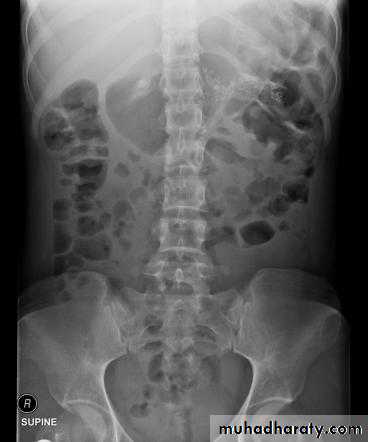

Dilatation of the bowel

Dilatation of the bowel is the cardinal plain film sign of intestinal obstruction

If the bowel is dilated it is important to try and decide which portion is involved

Large bowel obstruction

• Mechanical SB obstruction : small bowel dilation with normal or reduced caliber of colon• Mechanical LB obstruction: dilated colon down to the point of obstruction. May be accompanied by small bowel dilation if the ileocecal valve becomes incompetent